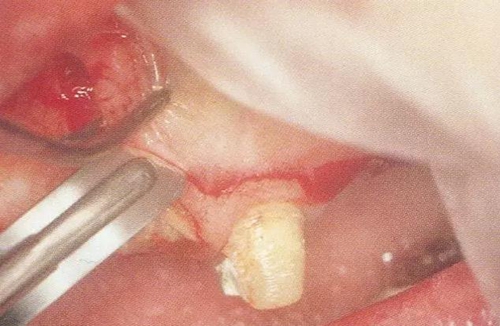

▼圖14-1(左)  用牙齦刀(ARUBA翻瓣器)將牙間部的牙間水平纖維以及牙槽嵴頂纖維切斷。

▼圖14-2(右)  將完全切割分離的組織用牙齦鉗將整塊比較容易的去除。

13.jpg